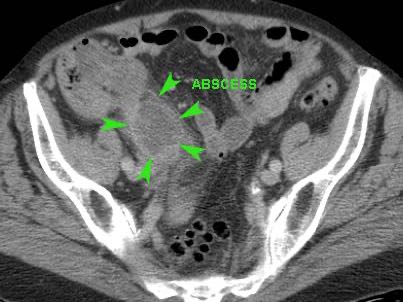

Dịch tự do

Một lượng nhỏ dịch trong phúc mạc giảm âm (*) có ít giá trị chẩn đoán và có thể gặp trong cả viêm ruột thừa cấp chưa thủng (trái) lẫn viêm ruột thừa thủng (mũi tên) (giữa), nhưng cũng có thể gặp ở bệnh nhân có ruột thừa bình thường (phải).

Lượng dịch lớn hơn, đặc biệt nếu khu trú và/hoặc đục, thường kèm theo liệt ruột khu trú hoặc toàn thể, là dấu hiệu nghi ngờ thủng.

Thông thường những bệnh nhân này có tình trạng nặng, đau nhiều và CRP tăng cao.

Ở người phụ nữ 56 tuổi này với CRP 180, siêu âm phát hiện dịch trong phúc mạc đục (*) và có thể thấy ruột thừa viêm với sỏi phân (mũi tên).

CT xác nhận hai sỏi phân ở hố chậu phải với hình ảnh khí bất thường, nghi ngờ viêm ruột thừa thủng.

Chọc hút dưới hướng dẫn siêu âm xác nhận dịch mủ.

Phẫu thuật cấp cứu phát hiện viêm ruột thừa thủng với nhiễm bẩn mủ bốn góc phần tư ổ bụng.